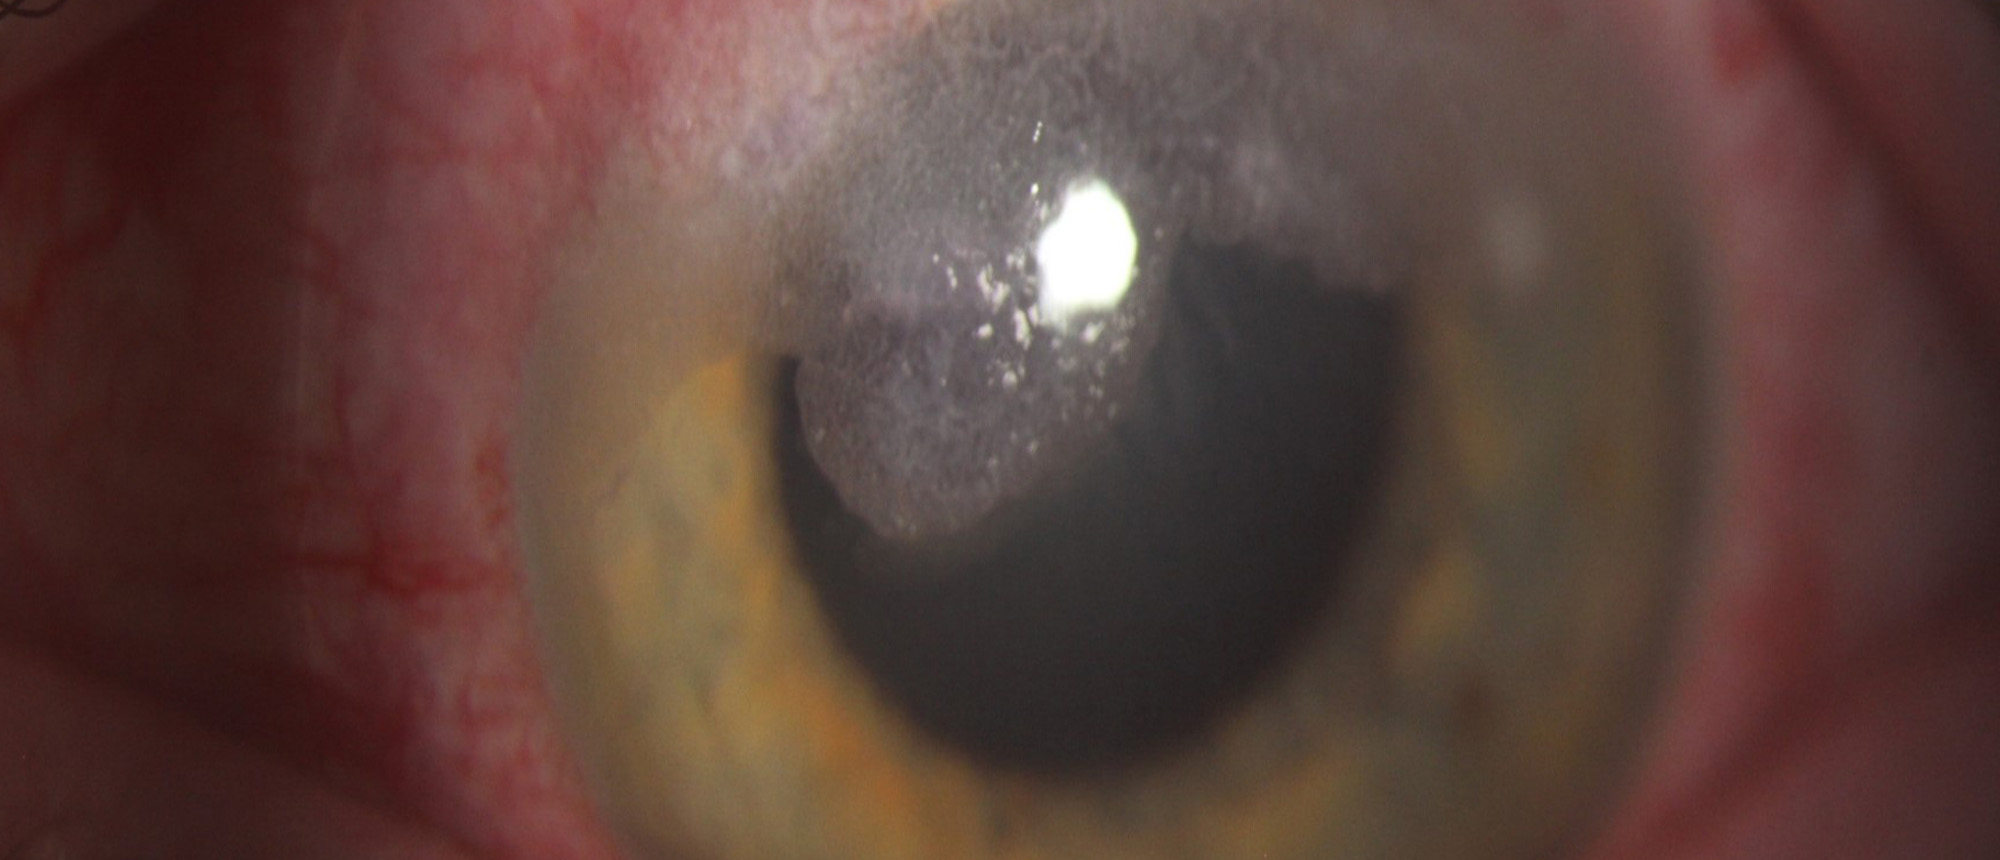

Abstract A patient with no pertinent ocular history presented with 3 months of pain, redness, and blurred vision in the right eye. Visual acuity was HM and slit lamp exam was remarkable for a central infiltrate with feathery irregular margins, significant injection, and a small hypopyon. The patien…

Fusarium Keratitis A patient with no pertinent ocular history presented with 3 months of pain, redness, and blurred vision in the right eye. Visual acuity was HM and slit lamp exam was remarkable for a central infiltrate with feathery irregular margins, significant injection, and a small hypopyon. …